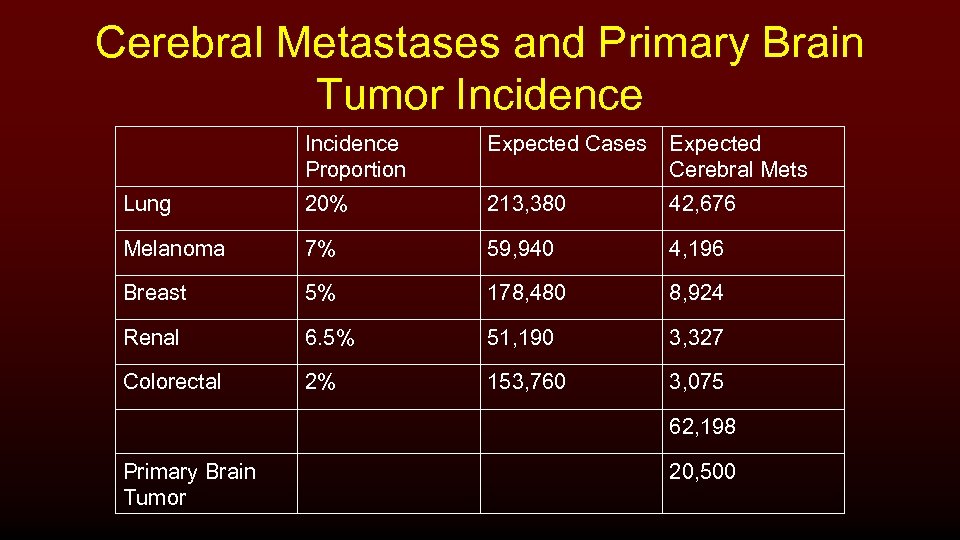

Cerebral Metastases and Primary Brain Tumor Incidence Proportion Expected Cases Expected Cerebral Mets Lung 20% 213, 380 42, 676 Melanoma 7% 59, 940 4, 196 Breast 5% 178, 480 8, 924 Renal 6. 5% 51, 190 3, 327 Colorectal 2% 153, 760 3, 075 62, 198 Primary Brain Tumor 20, 500